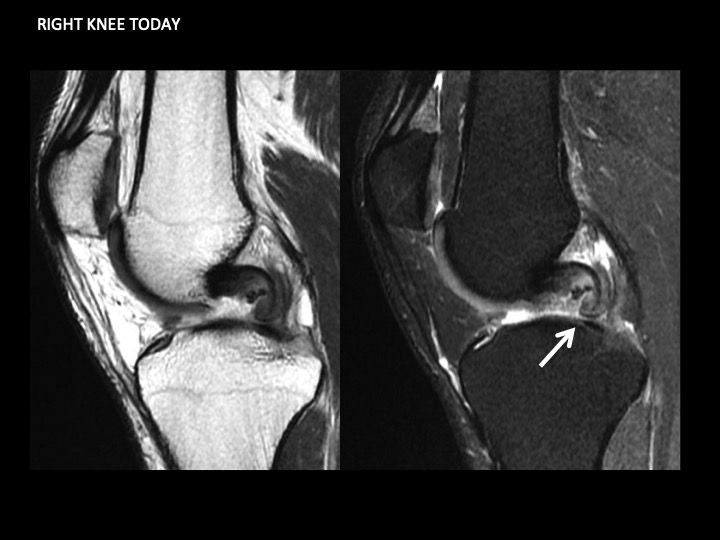

35M pain and swelling 1 month after fall playing basketball

There is intermediate signal soft tissue thickening along the medial aspect of the PCL with what appears to be a tear near the tibial insertion of the posteromedial bundle in the Sag images. The larger anterolateral bundle is intact, with minimal increased intrasubstance signal in the vertical segment. This is an isolated injury, so it will certainly be treated conservatively. I know there has been controversy over soft tissue thickening in this location, with reports of synovial thickening/scarring with intact PCL. Note that the opposite knee does not look like this (image 5). Even though this should heal with stability, I wonder if this might be the cause of scarring we sometimes see in this location and if it might not be a source of chronic pain and limitation. Thoughts? Reference article.

posteromedial bundle of posterior cruciate ligament ( RID2786 )